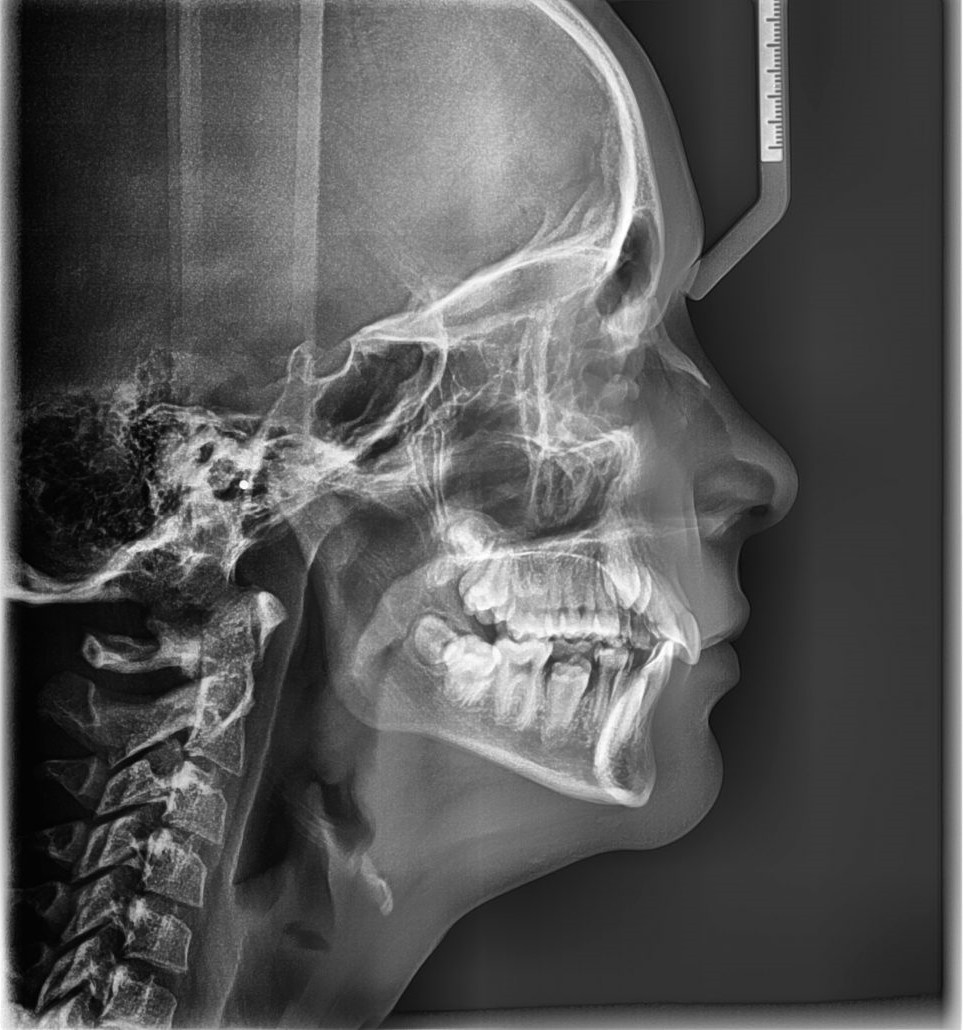

- Teleradiografie – imagine a întregului craniu, din faţă sau profil.